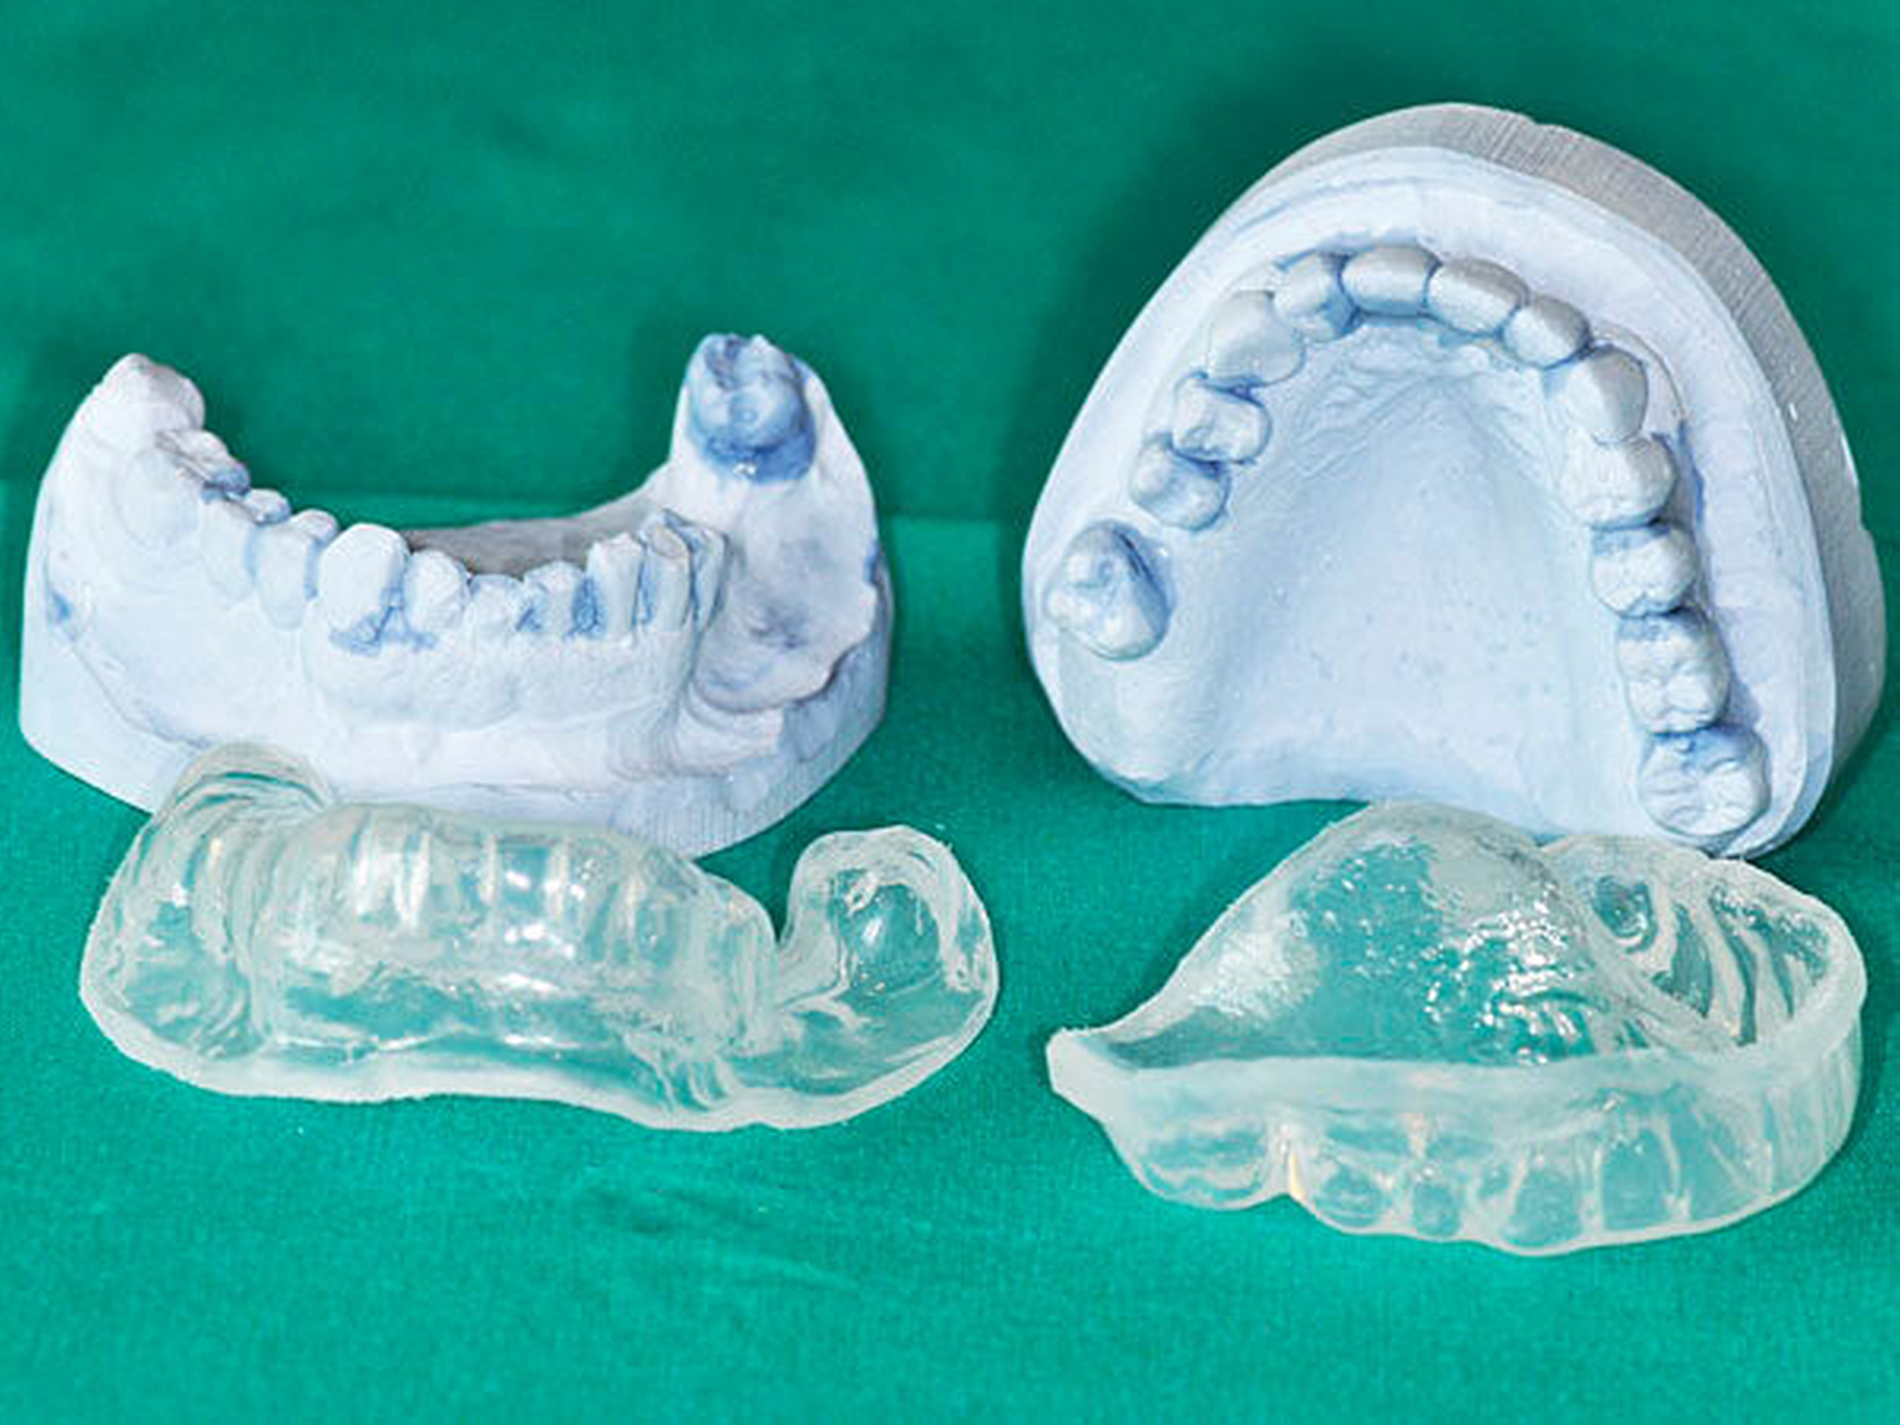

Oberste Priorität unter der Bestrahlung hat neben einer intensiven Mundhygiene die Gewebeschonung und das Vermeiden eines Unterbrechens der Strahlentherapie. Deshalb soll in der Phase der Bestrahlung bis zum Abheilen der radiogenen Akuttoxizitäten (circa sechs bis acht Wochen nach Abschluss der Strahlentherapie) auf jegliche zahnärztliche und chirurgische Behandlung, die mit einer Traumatisierung einhergeht, verzichtet werden [Chrcanovic et al., 2010]. Die Verwendung eines Schleimhautretraktors als Abstandhalter der Schleimhaut von metallischen dentalen Restaurationen auf Metallbasis oder beispielsweise Zirkonoxidgerüsten dient der Dosisreduktion durch Vermeidung von Streueffekten an der Oberfläche sehr dichter Materialien [Obinata et al., 2003] (Abbildung 3a).

Mehrere Studien verweisen auf den protektiven Effekt der topischen Fluoridierung bei Patienten nach Strahlentherapie zur Vermeidung einer radiogen bedingten Karies [Dreizen et al., 1977; Sennhenn-Kirchner et al., 2009]. Die Fluoridapplikation sollte nach Möglichkeit mittels Fluoridierungsschiene durchgeführt werden (Abbildung 3b). Entscheidend ist die lebenslange Durchführung. Die Prothesenkarenz unter Strahlentherapie und bei Mukositis dient der Vermeidung von Druckstellen. Die Morbidität der fortgeschrittenen IORN sowie das hohe Komplikationsrisiko rechtfertigen eine strukturierte und dauerhafte Nachsorge unter Inanspruchnahme professioneller Mundhygienemaßnahmen. Hierbei soll im Hinblick auf die Früherkennung einer IORN eine eingehende klinische Untersuchung der Mundhöhle erfolgen.